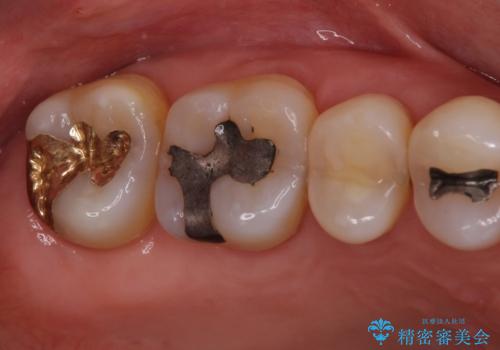

矯正治療後は、奥歯の虫歯や銀歯を補綴・修復治療することとしました。

上顎歯列を下顎に対して4mmほど移動させる必要があったため、治療は長期化することが予想されましたが、患者様にはこちらの期待以上にゴムかけなどに協力いただき、補綴治療も含めて2年強で終えることができました。